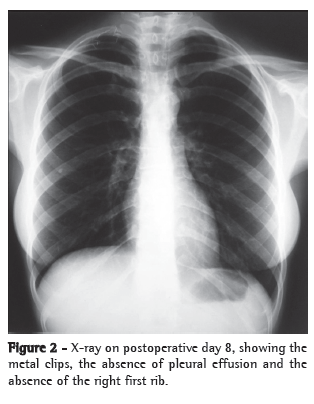

After the second intervention, the patient presented favorable evolution with a drastic decrease in chest drainage. On postoperative day 3, we introduced a diet with medium-chain triglycerides, although the diet was unrestricted from postoperative day 6 onward. On postoperative day 7, the chest tube was removed (Figure 2). The patient was discharged from the hospital on postoperative day 8, although still presenting difficulty in raising the right upper limb. After six months of follow-up treatment with an appropriate physical therapy program, the patient showed total recovery of the movements of the right upper limb. Pain and paresthesia ceased immediately after the surgery.